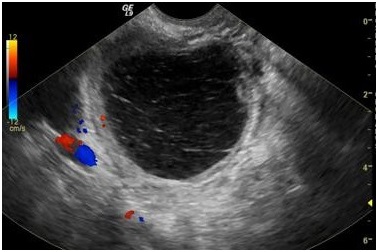

Так выглядит гиперэхогенное образование на экране УЗИ

Основным методом диагностики является ультразвуковое исследование (УЗИ) органов малого таза. УЗИ позволяет визуализировать матку и выявить наличие гиперэхогенных образований. Гиперэхогенные участки на УЗИ выглядят как светлые области, что указывает на их плотность и состав. Важно отметить, что гиперэхогенные образования могут быть как доброкачественными, так и злокачественными, поэтому дальнейшее обследование необходимо для уточнения диагноза.